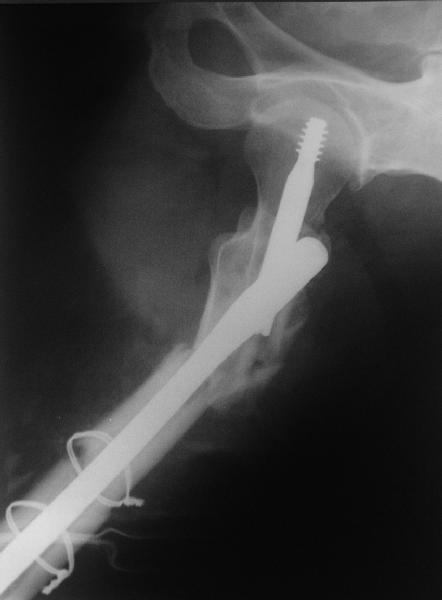

Мы получили испытательный вариант инструментария для пробы, хотя компания объявила, но ещё не для широкой публики, обещают к сентябрю. За полтора месяца, включая сегодняшнюю, вот уже восьмая операция по счету. Удобный инструментарий, ничего лишнего, научились делать быстро, посмотрим что будет, пока нравится.

Все больные пожилого возраста, первые уже успели появиться на амбулаторном приеме, пока без осложнений.

Здесь сканнированные снимки импланта и операционные снимки больной.

На этом снимке процесс компрессии нижним болтом.

Итог